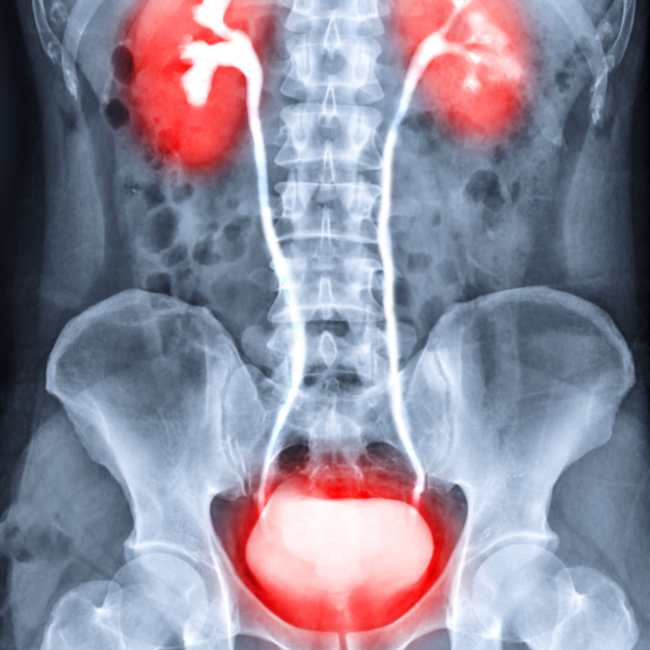

과민성 방광 증후군의 치료

과민성 방광 증후군의 예방

명확한 예방법이 있는 것은 아니지만 다음 사항들이 증상 발생을 줄이는데 도움이 되리라 생각합니다.